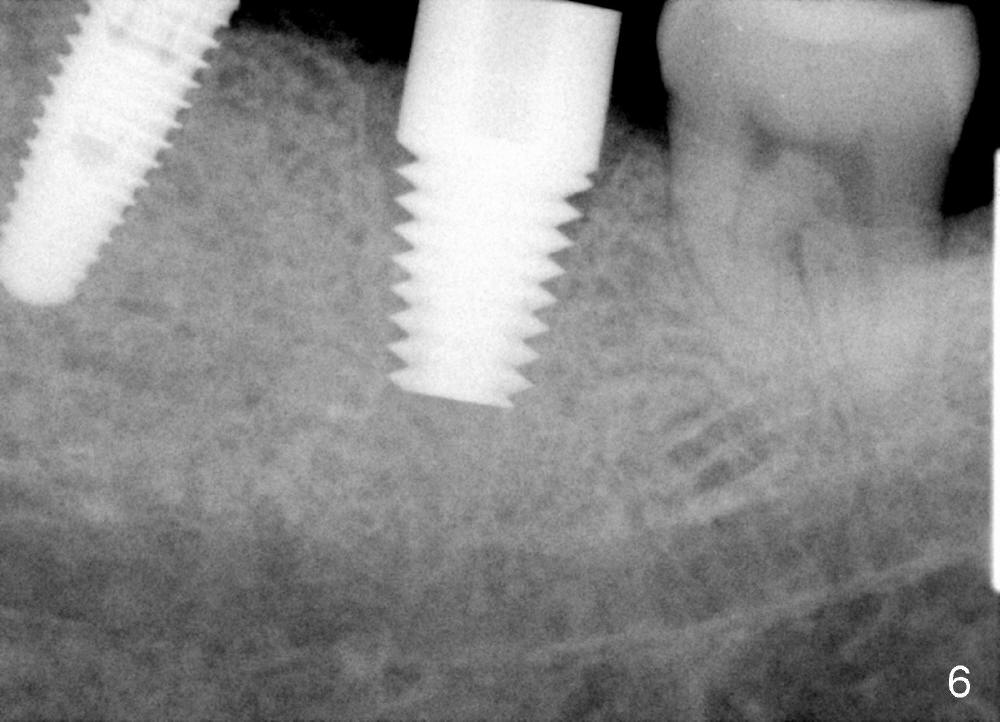

The septum of the socket is thin (Fig.3*), and easily removed, leaving a large socket. Osteotomy is initiated with 2 mm pilot drill in the middle of the socket, slightly mesiolingual, since the buccal and distal bone is low and defective. Reamers (2.5 to 4 mm in diameter) are sequentially used to enlarge osteotomy and harvest autogenous bone (Fig.4 (3 mm reamer in place). When 5 mm tap is placed, there is no stability. Six mm tap gains some stability, but the socket is not closed. Seven mm tap achieves strong stability and is closing the socket (Fig.5). Ultimately a 7x14 mm implant is placed with insertion torque more than 60 Ncm (Fig.6). The implant almost obliterates the socket (Fig.7). The harvested autogenous bone is placed in the buccal and distal aspects of the socket before Chromic gut suture (4-0) is placed distally. Fig.8,9 show the healing socket 6 days and 1.5 months postop, respectively. Osteointegration appears to occur in 2.5 months (Fig.10, compare to Fig.6). Bone level remains the same 1 year post cementation (Fig.11).